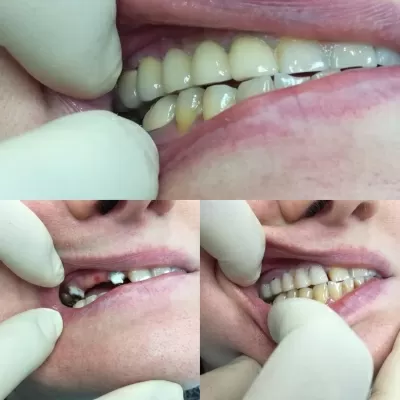

Недавно столкнулась с проблемой кариеса на верхнем и нижнем зубах. Зубная боль оказалась очень сильной, поэтому решила, как можно скорее, посетить стоматолога. Выбор пал на клинику ЛигаДент, так как слышала положительные отзывы о ней, и она не так далеко от дома. Позвонила туда, администратор в считанные минуты записала меня на прием в нужное время. Первые минуты в кресле сид